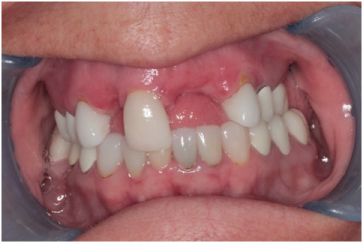

The patient is a 52-year-old female with a non-contributory medical history. The patient was missing teeth #s 7, 9 and 10 and she was interested in replacing these teeth with dental implants. A Cone Beam Computer Tomography (CBCT) of the maxillary arch was completed and reviewed with a clinical evaluation also (Figure 1, Figure 2, and Figure 3). Significant labial concavities and bone atrophy was noted and guided bone regeneration (GBR) was recommended using a d-PTFE, Cytoplast® titanium reinforced membrane (Osteogenics Biomedical, Lubbock, TX, USA).

Figure 1: Labial concavity at the #s 7, 9, and 10 sites. View Figure 1